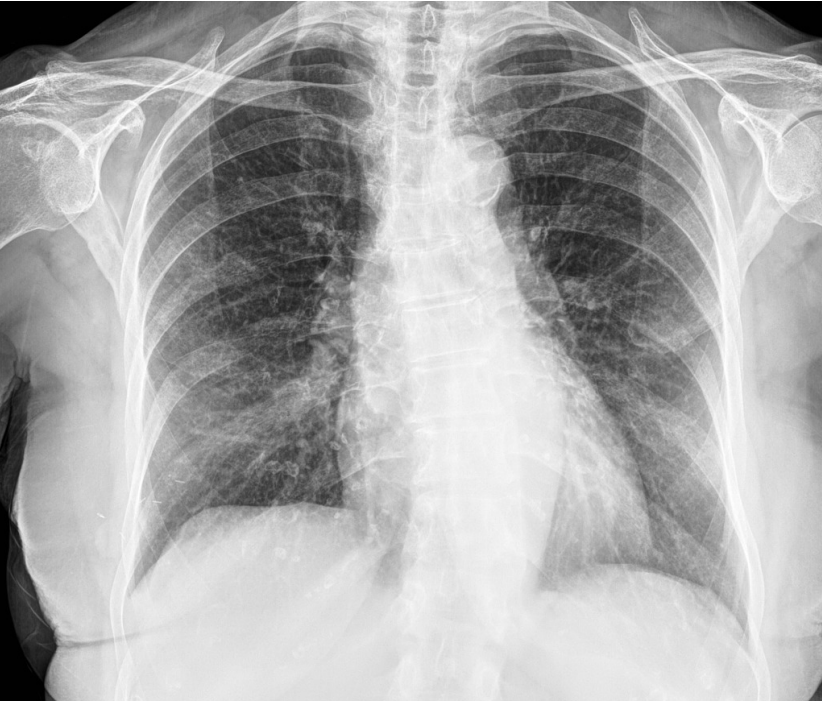

Refer to caption

Fig 3. COVID-19